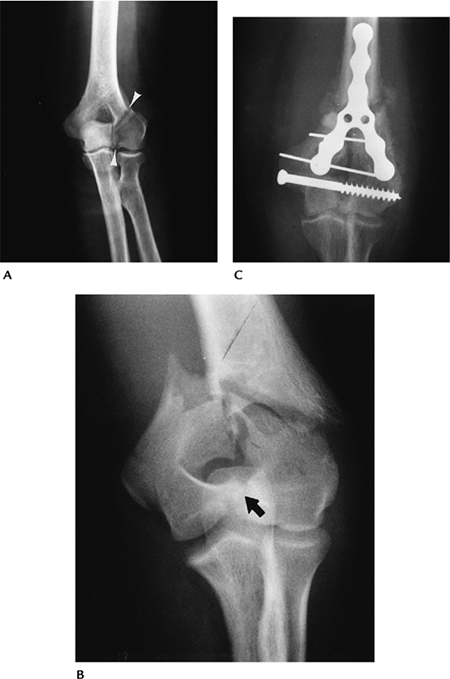

![]() |

FIGURE 8-6 AP radiograph of a lateral column fracture entering the margin of the trochlea (arrowheads). (B) AP radiograph of an intra-articular “T” fracture. (C) AP radiograph after internal fixation of a “Y”-type fracture.